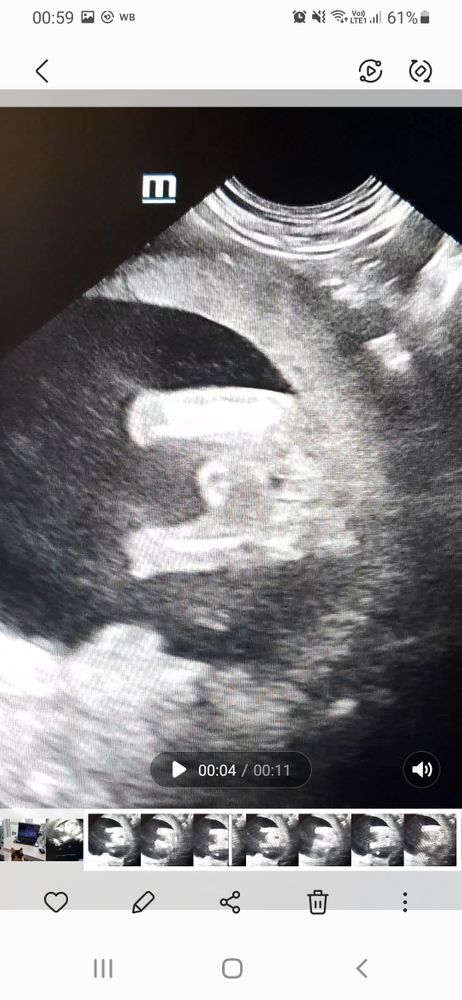

Девочка же? Узи 16 неделя, вид снизу

Больше на мальчишку похоже

На втором фото прям половая щель видна))) как по мне то девочка) Изображение Вот так наш пацан выглядел на УЗИ)

Может ракурс конечно такой, но вообще у нас по другому «три полоски» выглядели, не выпирали так Но вроде на девочку похоже да)

Девочка на нижнем фото видно , просто губки опухли

Писюна нет, пирожок есть но как то странно. У моей было немного по другому

А врачь вам разве не сказал? На нижнем девочка, а верхнее не очень удачный ракурс, писюн может и вверх смотреть и на бок

Соня , врач на узи сказала, что не понятно, т.к. ребёнок ножки поднимал и пуповина мешала. Эти снимки я сама себе делала, я ветеринарный узист😄

Мальчик) мне сейчас делали УЗИ и вообще гладенько все было и сказали, что девочка, а тут все видно)

Леся, по мне так отчётливо 2 яйца)